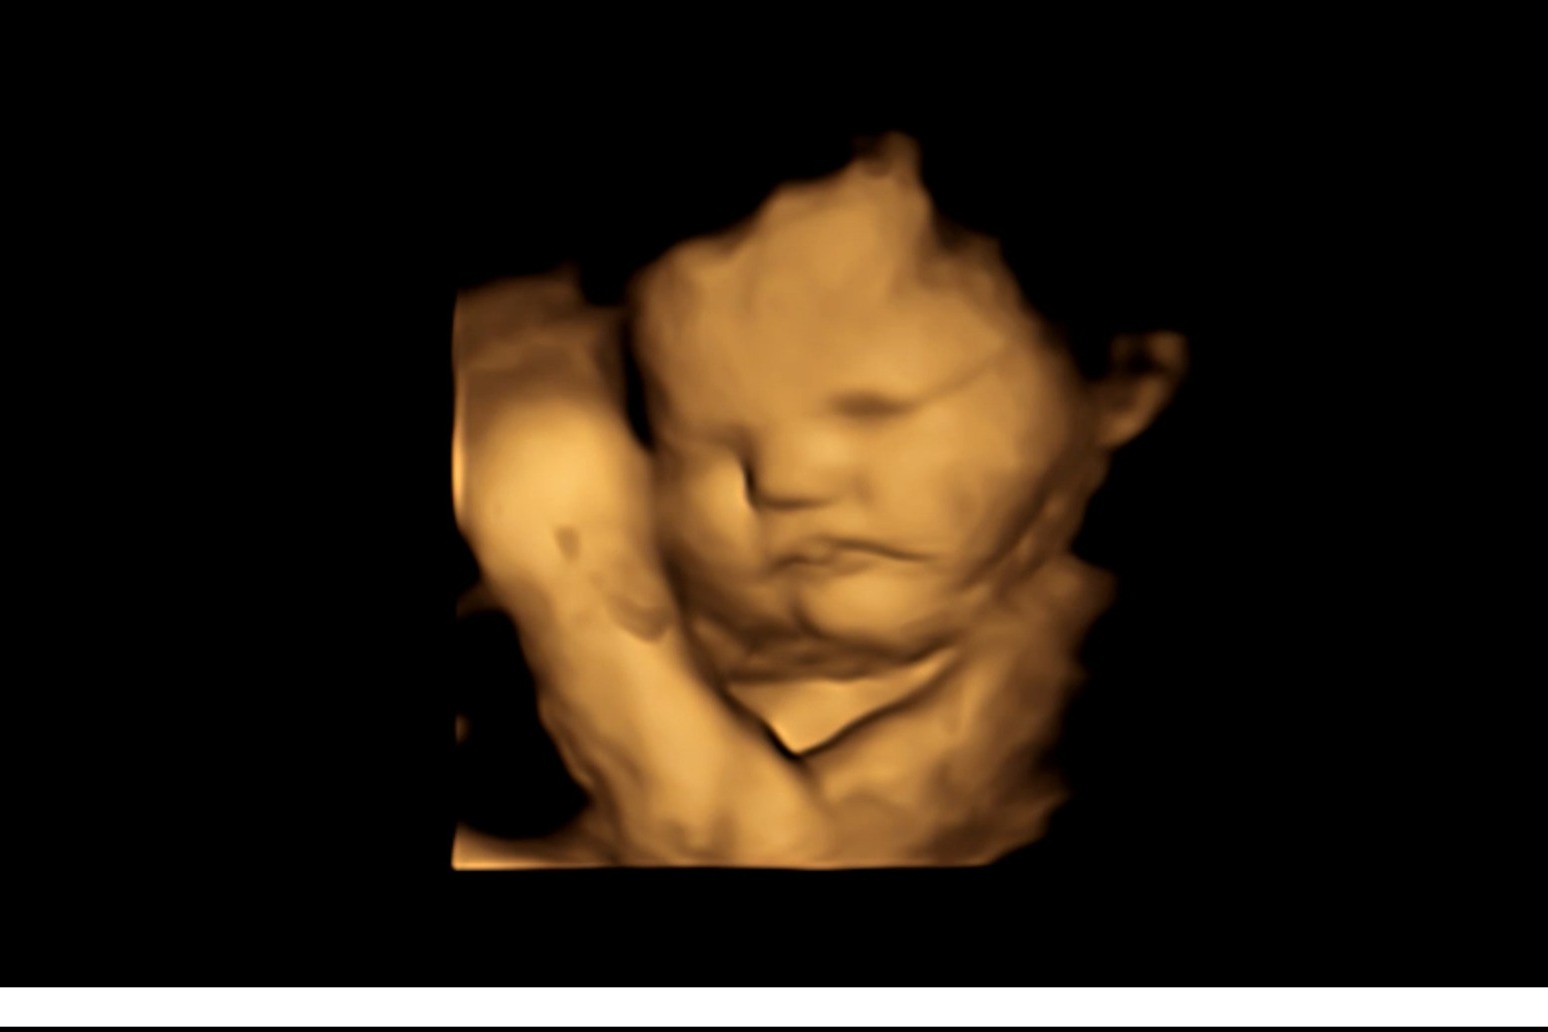

For the first time, scientists recorded evidence that babies react differently to various smells and tastes while in the womb by recording their facial expressions.

Experts from Durham University took 4D ultrasound scans of 100 pregnant women to study how their unborn babies responded after being exposed to flavours from foods eaten by their mothers.

Foetuses exposed to carrot showed more ‘laughter-face’ responses while those exposed to kale showed more ‘cry-face’ responses.

Mothers were scanned at 32 and 36 weeks pregnancy to see foetal facial reactions to the kale and carrot flavours.

Facial reactions seen in both flavour groups, compared with foetuses in a control group who were not exposed to either flavour, showed that exposure to just a small amount of carrot or kale flavour was enough to stimulate a reaction.